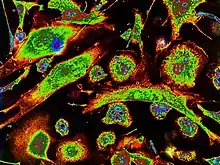

Structurally, epithelioid cells (when examined by light microscopy after stained with hematoxylin and eosin), are elongated, with finely granular, pale eosinophilic (pink) cytoplasm, and central, ovoid nuclei (oval or elongate), which are less dense than that of a lymphocyte.[4] They have indistinct shape and often appear to merge into one another, forming aggregates known as giant cells. When examined by transmission electron microscopy in epithelioid cells in the field of Golgi lamellar complex are taped not only zonated, but also sleek vesicles with dense center, and also great many (more than 100) large granulas with diameters up to 340 nm and with finegranular matrix more light than in macrophage granulas, sometimes with perigranular halo. “The most prominent feature of these cells is the enormous Golgi area; up to 6 individual stacks of Golgi cisternae may be present as well as a few bristle-coated and numerous smooth vesicles”.[5][4] Epithelioid cells have tightly interdigitated cell membranes in zipper-like arrays that link adjacent cells.[3] This cells are central in the formation of granulomas, which are associated with many serious diseases.[4] In granulomas, epithelioid cells perform the functions of delimiting.[3]

It is shown that the epithelioid cell cytoskeleton formed by filaments differs significantly from the macrophage cytoskeleton.[6][7] A large increase in the number of filaments occurs in these cells, where filaments (90 to 100 A) surround the cytocentrum as a distinctive annular bundle often branching into the cytoplasm. Due to such cytoskeleton contiguous epithelioid cells display elaborate cytoplasmic interdigitation.[6] By using the quick=freeze and freeze-substitution methods (prompt freezing, penetrating etching and freeze-substitution) it has been shown that the organizations three-dimensional metastructure cytoskeleton of the epithelioid cells, formed in the focus of granulomatous inflammation, more compatible to cytoskeleton characteristic of typical epithelial cell than to cytoskeleton of active and movable macrophages. It is exhibited that the dense webs of intermediate filaments, bound with cores, mitochondrions and other organelles, are supervised everywhere in cytoplasm of epithelioid cells. Some fascicles of actinic filaments were posed in filopodiums below than membranes of the cells. Exact interdigital tripling of membranes of cells between interfacing epithelioid cells were clearly demonstrated. Interdigital filopodiums were identified. The characteristic indication of epithelioid cells is their aggregation with formation tight interdigital triplings as a fastener "lightning", which, apparently, can have the important for the formation of a dense zone of delimitation of the body from the pathogen during the formation of epithelioid cell granulomas.[7]